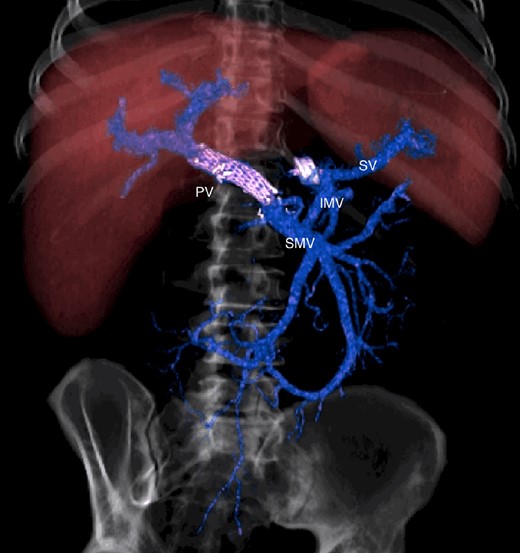

CT scan after other interventional radiology with plug in the splenic vein and cover stent in the superior mesenteric vein. PV portal vein, SMV superior mesenteric vein, SV splenic vein, IMV inferior mesenteric vein.

CT scan at 3 years, with development of venous collaterals that drain distal splenic vein and inferior mesenteric vein through the lesser omentum. PV portal vein, SMV superior mesenteric vein, SV splenic vein, IMV inferior mesenteric vein, CV collateral veins.